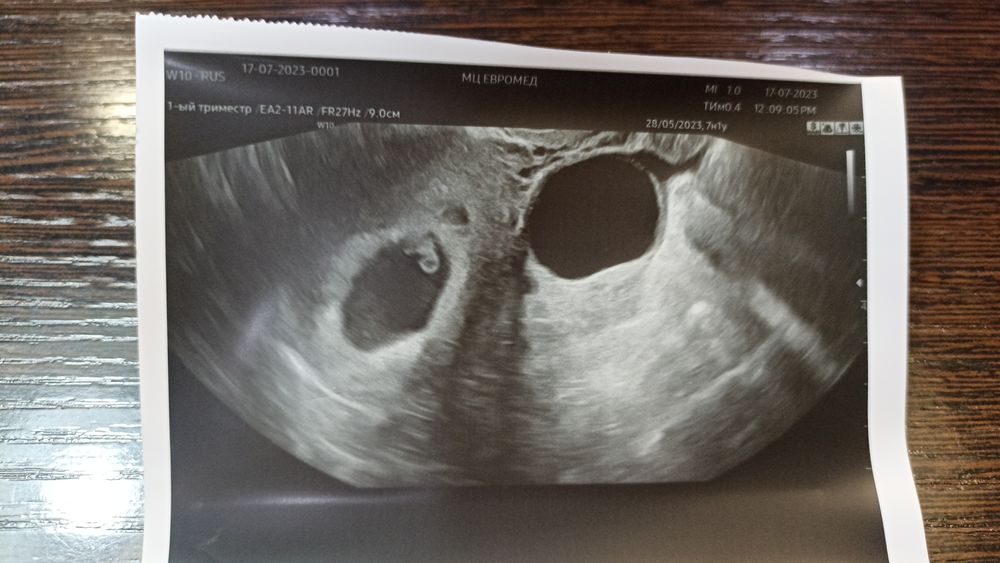

Девочки, помогите разобраться. Приехала с УЗИ, 7 недель 1 день это акушерский, от последних м (28.05), Почему плодное яйцо на 7 недель и 3 дня? Овуляция была 15.06. ПА 14 и 16. Т. е. в среднем 4 недели 4 дня от зачатия. Может ли быть, что двойня однояйцевая?

Пя одно, эмбрион один,при чем тут двойня? А размер пя зависит от роста хгч,чем быстрее хгч растет,тем быстрее пя растет и может быть больше,но это наооброт хорошо, размер пя роли не играет,срок ставят по размеру эмбриона (ктр), а пя может быть разное,у меня тоже пя больше было на неделю пя на 7 недель,а эмбрион на 6 недель,и акушерский срок тоже 6 недель был и все по сроку

Алёна Меньшикова, а что вас смущает? От овуляции у вас прошло 32 дня,а это 4+4 от зачатия,а акушерский на 2 недели больше,т.е 6+4,у вас эмбрион на 6+5 все по сроку,а акушерский от месячных может быть и больше,смотря когда овуляция была,если позже 14 дня,то и срок может отличаться,т.е если овуляция на 17 д.ц по УЗИ может срок быть меньше на 2-3 дня и это норма,а плодное может быть хоть на 8 недель,по нему срок не оценивают,эта величина вариабельная и у всех на одном сроке можно отличаться,по УЗИ тоже акушерский срок ставят по размеру эмбриона,с нормальной овуляцией срок по УЗИ и по месячным практически совпадает,с поздней овуляцией по УЗИ срок соответственно меньше может быть,с ранней больше,а от зачатия срок нигде не считают,если вы это имели ввиду

P.s у вас все совпадает идеально по сроку 7,1 по месячным,а овуляция на 17 д.ц,т.е срок по УЗИ должен быть на 3 дня меньше,так как овуляция была на 3 дня позже,вот у вас по УЗИ эмбрион на 6+5 как и должен быть,вот эти 3 дня и вылезли в сроке,была б овуляция ровно на 14 д.ц,то у вас бы и по месячным и по УЗИ был бы срок 7,1

Виктория

У вас просто плодное яйцо быстрей растет и все, тут разница в 2 дня, она вообще не существенная, еще учитывайте погрешности УЗИ. на таком строке уже видно однояйцевую двойню + у вас в заключение стоит один эмбрион. Вообще ничего критичного не вижу, беременность развивается согласно сроку

Скорее всего это означает только то, что размер плодного яйца больше, чем нормы для срока 7+1. Поэтому и пишут 7+3